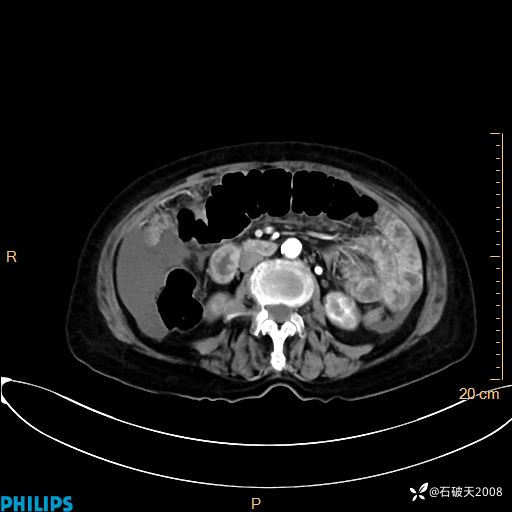

平扫